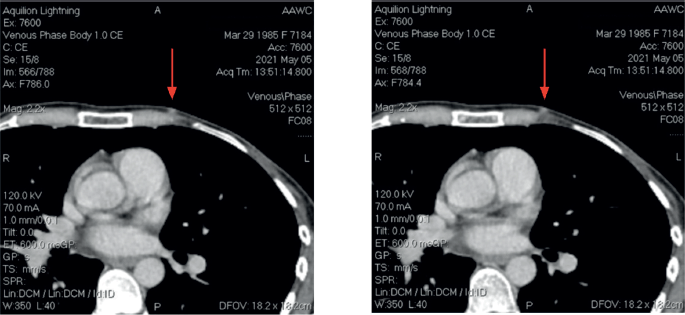

After the second postoperative cycle, the patient palpated three new subcutaneous nodules on the left chest wall, confirmed by CT scan (Figure 2). No distant metastases were identified. A fourth surgery focused on the removal of subcutaneous lesions. Postoperative pathology confirmed breast cancer in all three specimens. The tumour board recommended postoperative radiotherapy (RT) and hormonal therapy with AI ± CDK4/6 inhibitors. The patients went abroad to Germany, where new left axillary lymphadenopathy was found. The patient had another surgery: left axillary lymph node dissection. Afterward, she received RT combined with Capecitabine and two cycles of Capecitabine after RT. However, follow up with a CT scan revealed recurrence with new lesions in the liver. Treatment was adjusted to Ribociclib plus Fulvestrant, which she received for 5 months without a major response.

Figure 2. CT Images at third recurrence.